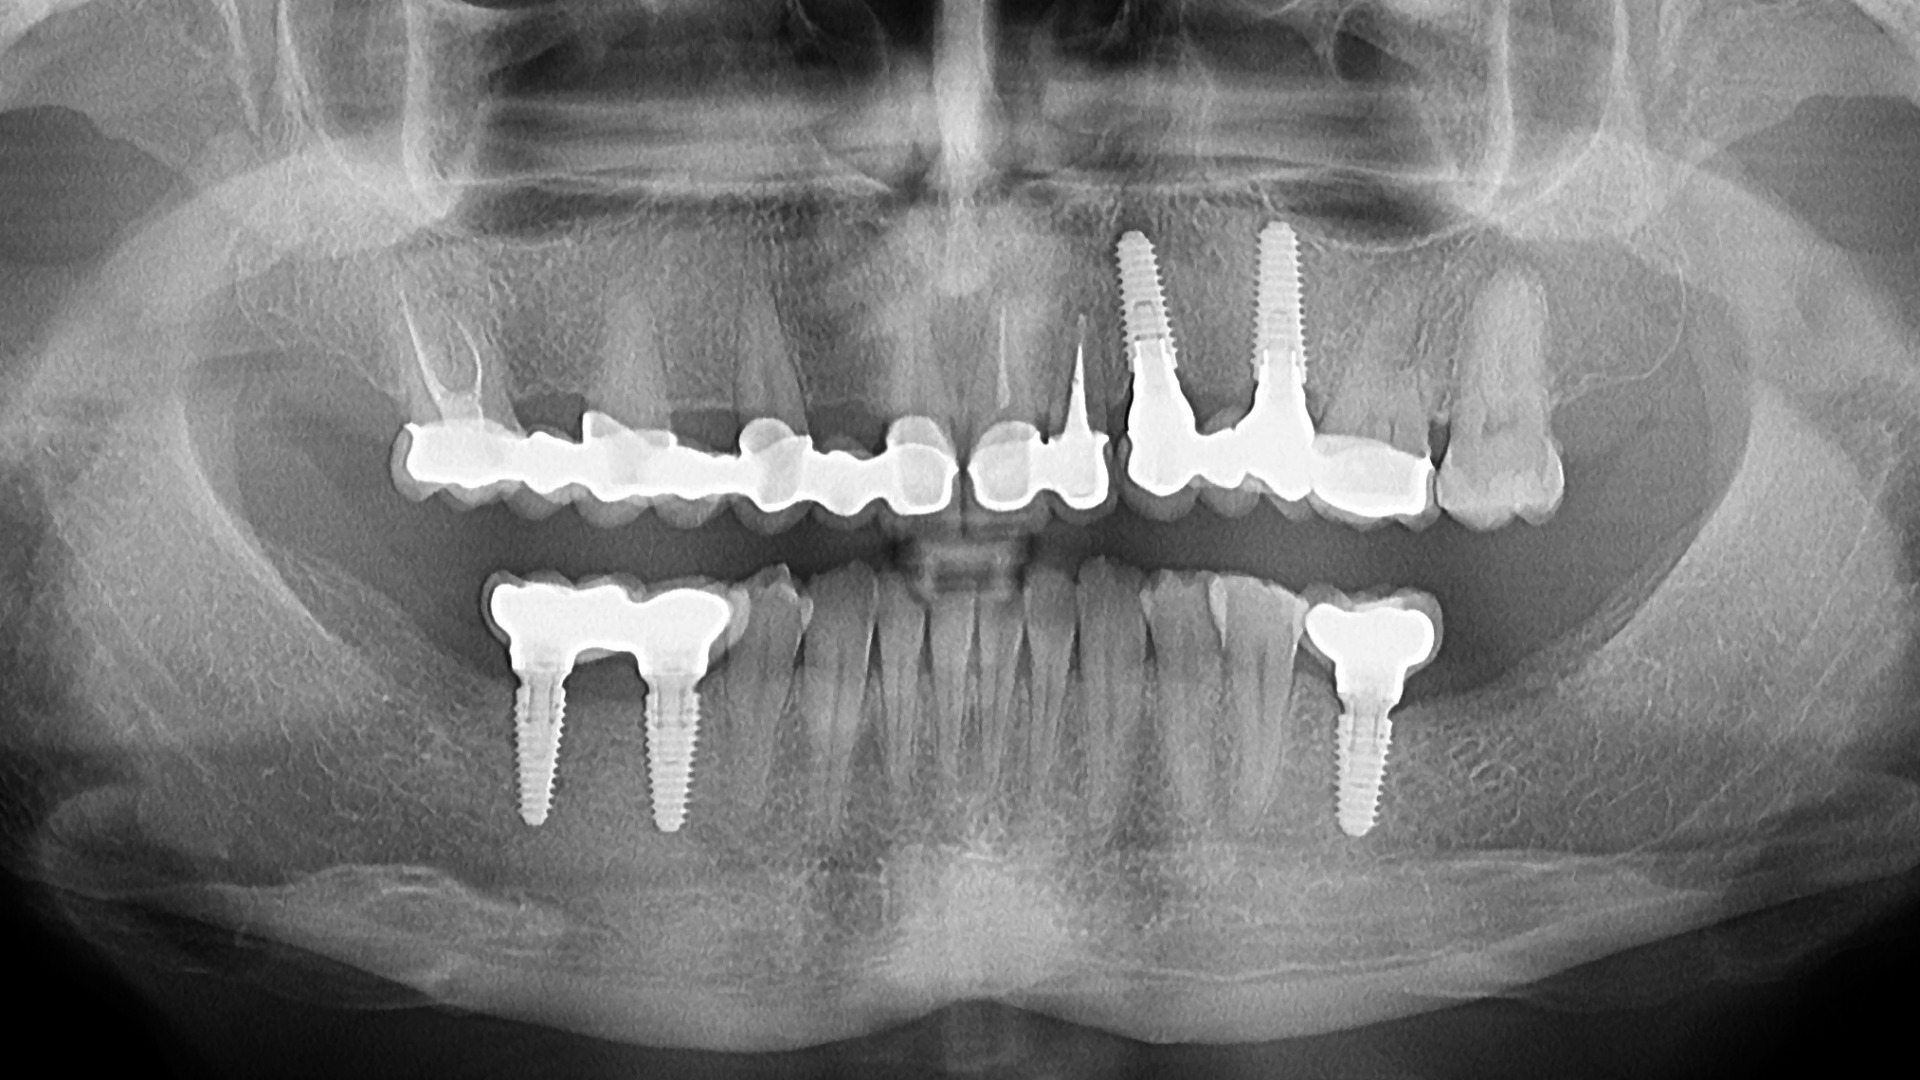

Ortopantomografia oferă o imagine panoramică a maxilarului, a mandibulei, a sinusurilor maxilare și a articulațiilor temporo-mandibulare.

Se poate efectua atât la adulți, cât și la copii, doza de radiații fiind minimă, iar timpul de expunere foarte scurt. În cazul copiilor, radiografia panoramică ne ajută să evaluăm și evoluția erupției dentare. Deși radiațiile X sunt nocive pentru sănătate, aparatura digitală de ultimă generație expune corpul uman la o doză de radiații extrem de redusă, similară celei produse de un televizor în câteva ore de vizionare sau celei rezultate în urma unei plimbări dintr-o zi însorită.